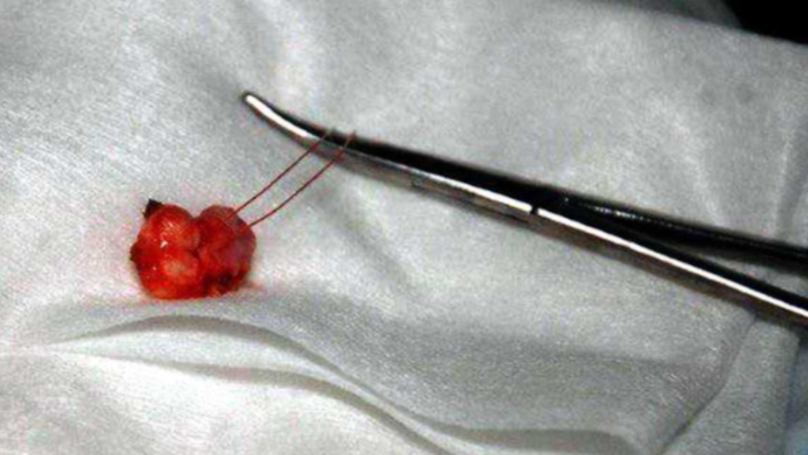

But they were stunned the moment they found out that the cause of the lump was a molar tooth which was missing from his mouth and grew in his testicle instead.

The rare surgery was carried out by surgeon Dmitry Tarusin, and it is believed the boy can still have good reproductive health.

“The surgery proved that the real seventh tooth – a molar – was growing inside the testicle, the one that was missing in the jaw.